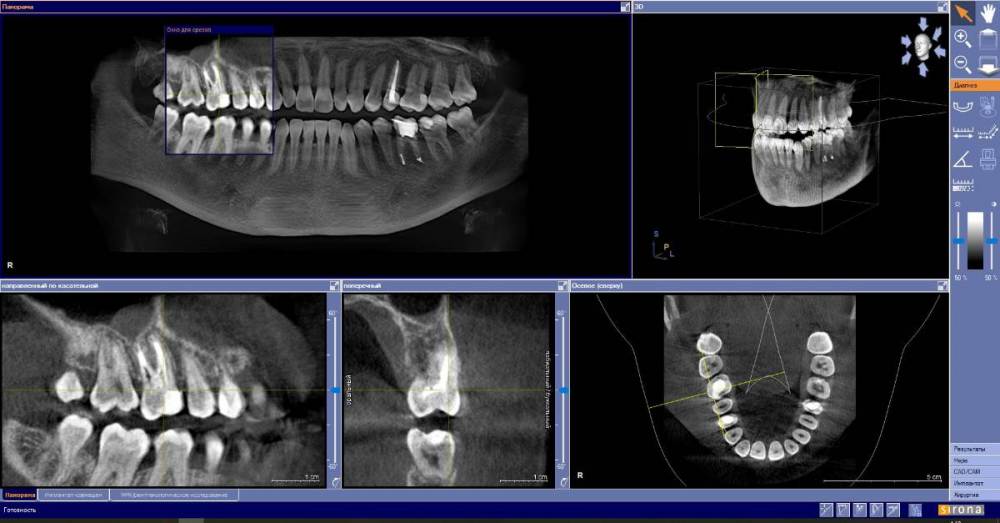

anishuma Опубликовано 1 сентября, 2021 Поделиться Опубликовано 1 сентября, 2021 (изменено) Здравствуйте, прошу помочь разобраться с моими КТ и направить для дальнейших действий. История такая: в 2018 году шестой зуб сверху справа был депульпирован. Долго сохранялись боли при нажатии, при жевании, зуб реагировал на холодной и горячее. Врач, который лечил, заверила что это постпломбировочные боли и скоро пройдет. Коронку побоялась ставить из-за этих болей. Затем примерно через год отлетел кусочек пломбы. Зуб восстановили для дальнейшей установки коронки. На данный момент есть ощутимая реакция на давление, при жевании, при чистки зубной щеткой. Зуб реагирует на холодное-горячее. Один врач сказал, что не видит показаний для перелечивания каналов. Другой врач настаивает на удалении зуба. Подскажите, пожалуйста, где истина, и возможно ли сохранить зуб. Изменено 1 сентября, 2021 пользователем anishuma Ссылка на комментарий

Bier Опубликовано 2 сентября, 2021 Поделиться Опубликовано 2 сентября, 2021 похоже что есть гранулема на корне 2 Ссылка на комментарий

St. Опубликовано 3 сентября, 2021 Поделиться Опубликовано 3 сентября, 2021 +1 к гранулеме. Я бы перелечивала каналы. Но нужно в процессе будет смотреть нет ли трещин в корне. Ссылка на комментарий